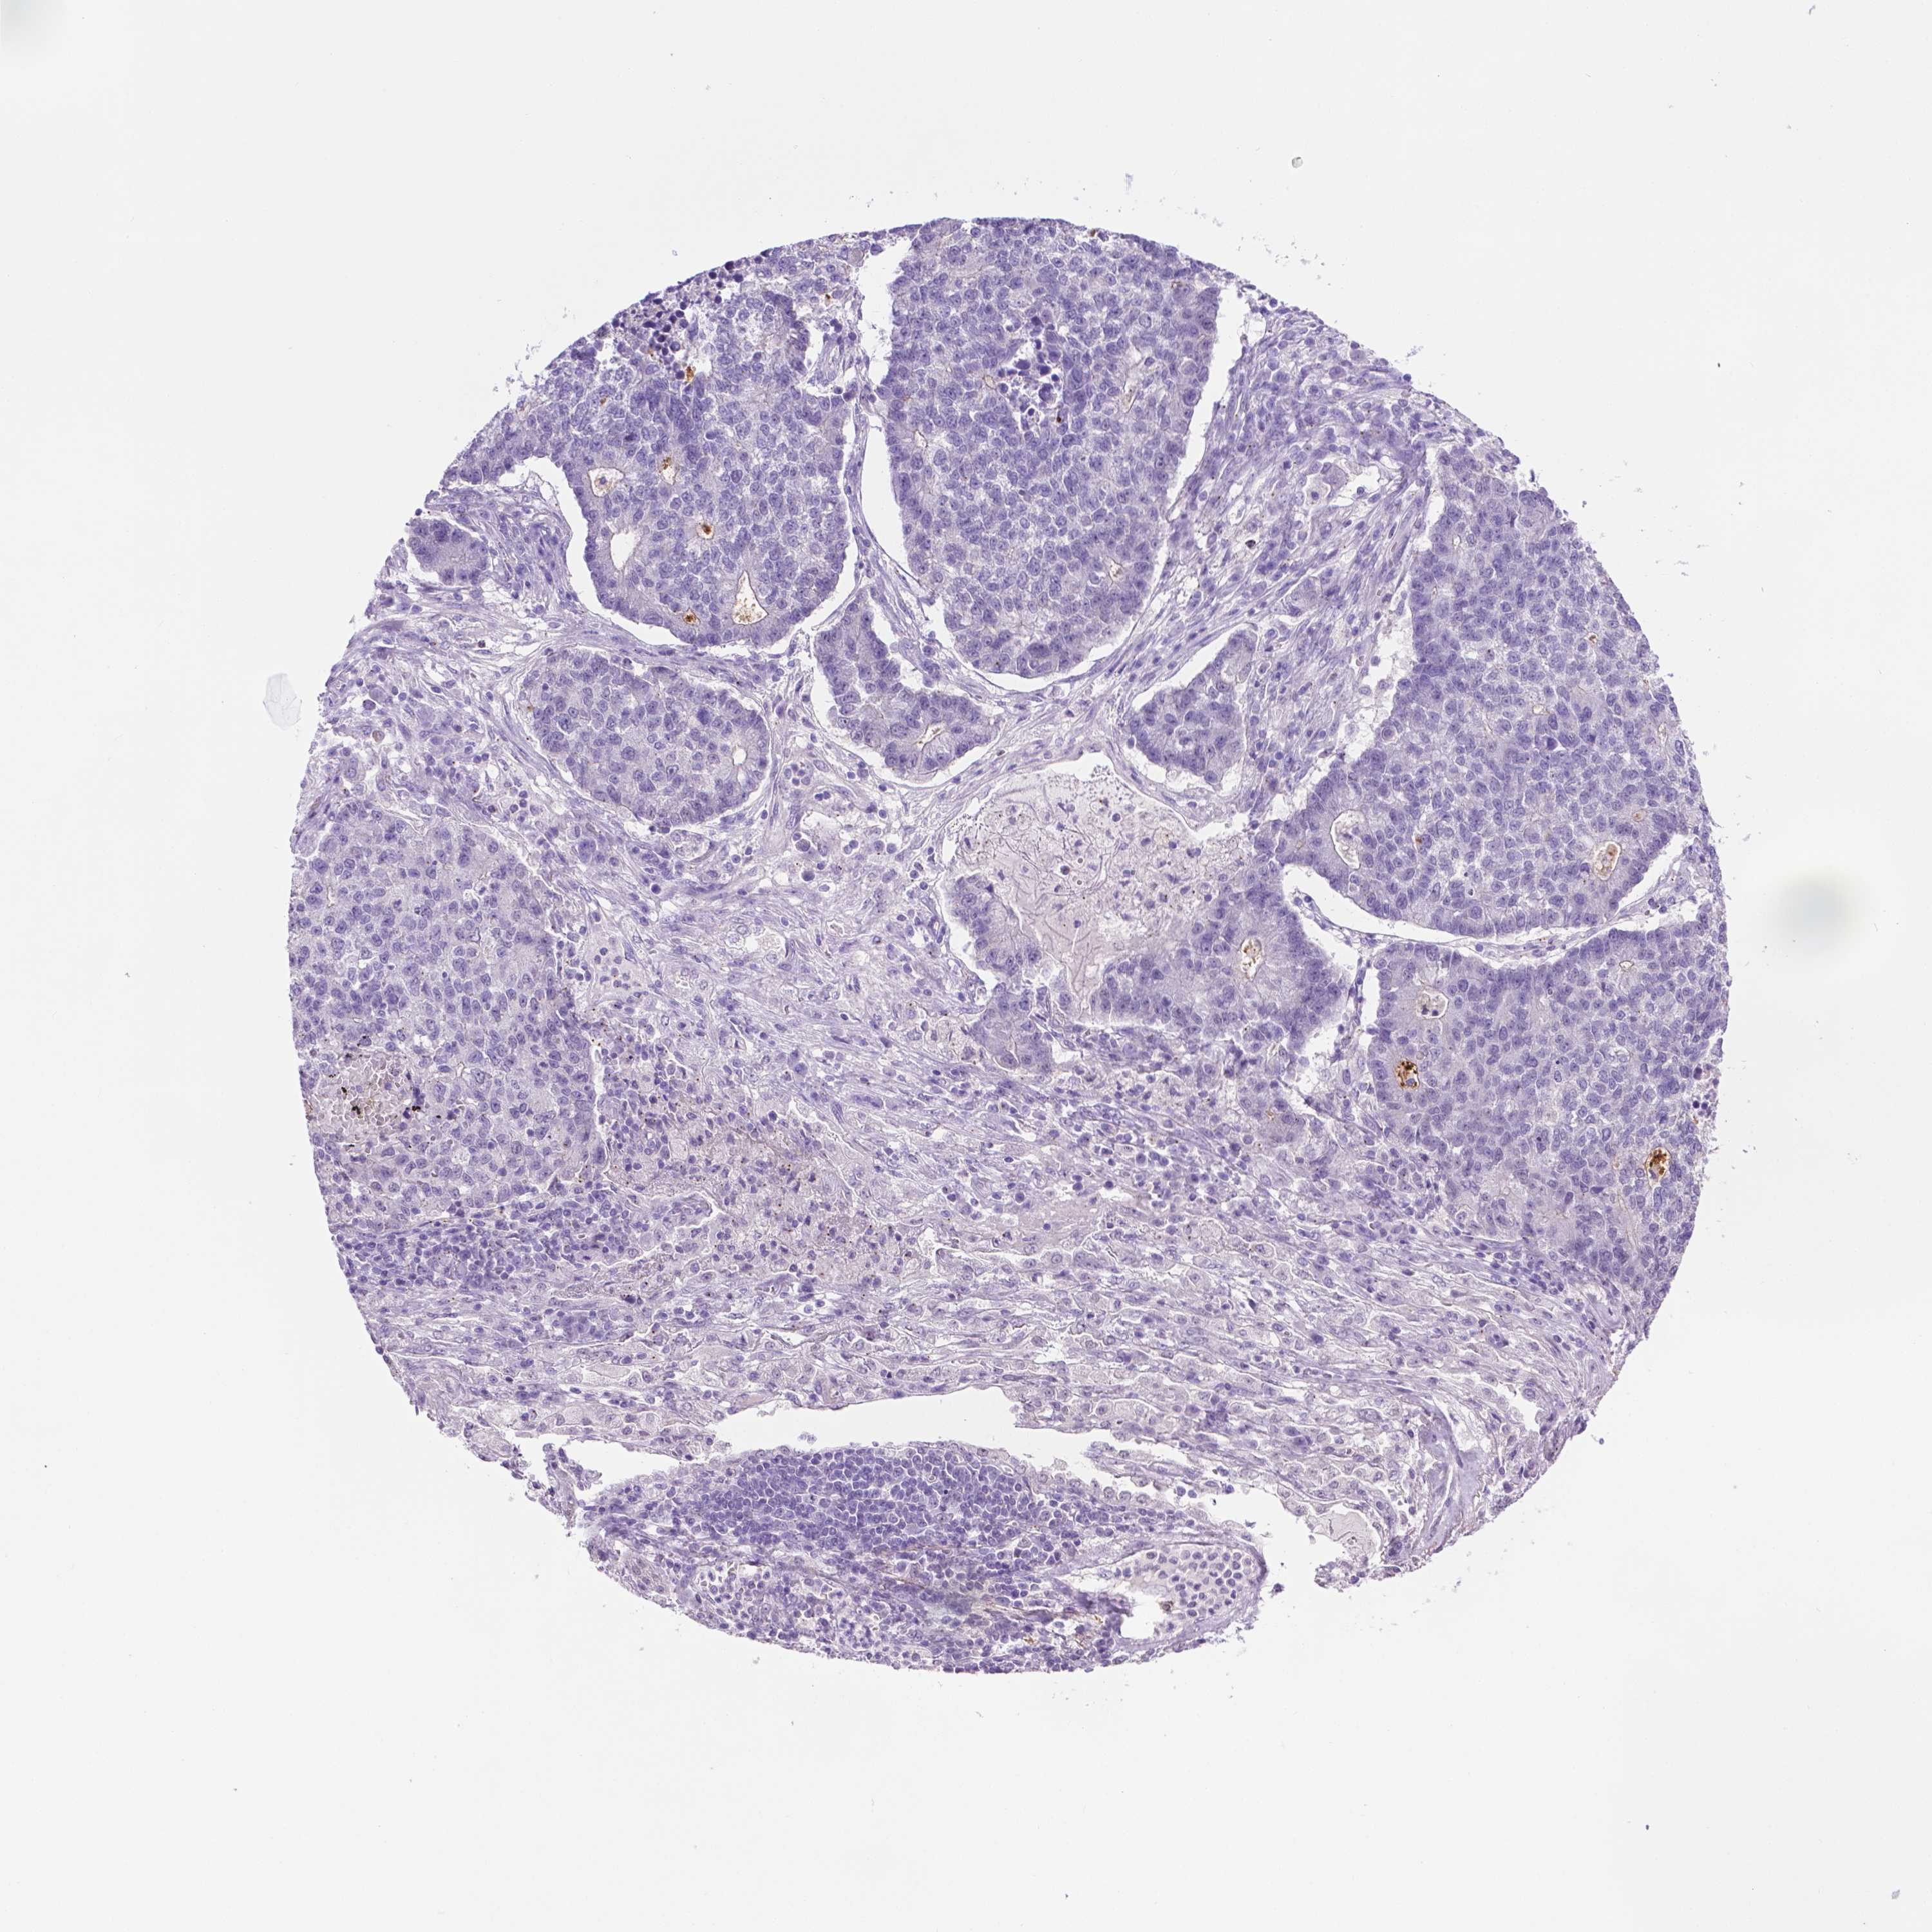

MMP27 is not prognostic in Lung Squamous Cell Carcinoma (TCGA)

TCGA RNA samplesi

RNA-seq data is reported as average FPKM (number Fragments Per Kilobase of exon per Million reads), generated by the The Cancer Genome Atlas (TCGA) .

Normal distribution across the dataset is visualized with box plots, shown as median and 25th and 75th percentiles. Points are displayed as outliers if they are above or below 1.5 times the interquartile range. FPKM values of the individual samples are presented next to the box plot.

Average pTPM 0.0

Number of samples 489